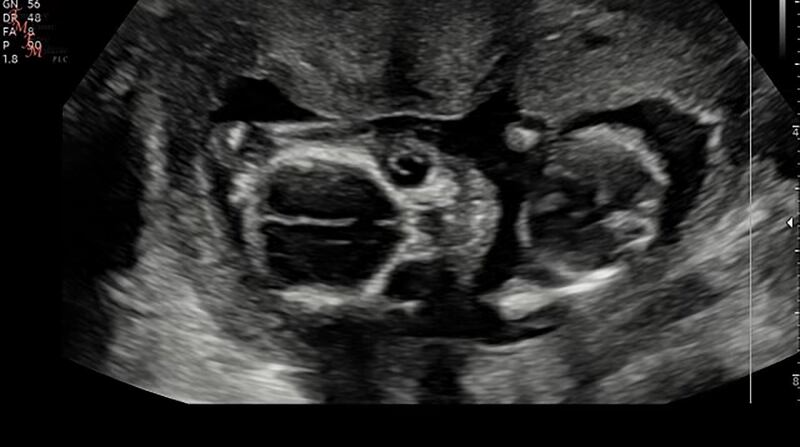

The doctor entered and directed Phillips’ attention to the screen and a gap in a white line down the middle of her baby’s brain. The doctor explained that the gap showed the brain had not fully divided into the right and left hemispheres.

A sonogram shows the gap in the line between the hemispheres of the brain.

Courtesy Ally PhillipsThe doctor said it was a rare congenital defect known as holoprosencephaly (HPE). Only 3 percent of fetuses with it survive to birth.